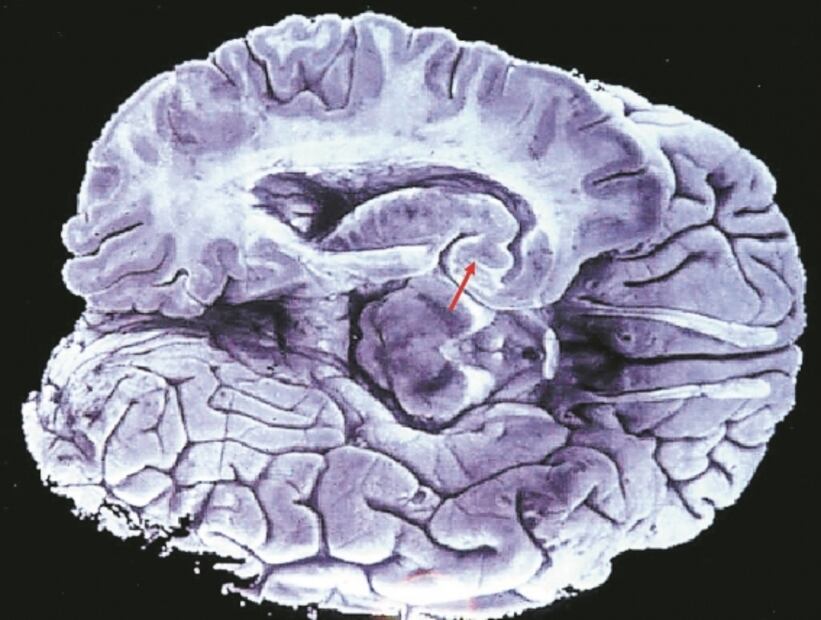

Radiografía de un cerebro con Alzheimer. Foto: Archivo